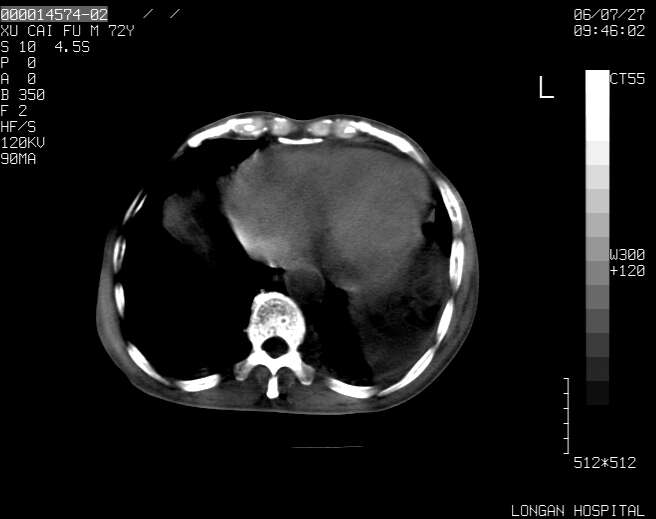

以下是引用winter在2006-7-30 20:14:00的发言:[br]1、考虑胆囊癌伴胆道侵犯并高位胆道梗阻、肝内多发转移、腹膜后淋巴结转移。[br]2、右肾轻度积水。[br]3、老人家72岁了胰腺头体尾部均较饱满,不过未见密度异常及其他异常征象。[br]4、腹水。

以下是引用jiajie在2006-7-31 7:10:00的发言:[br]考虑肝转移瘤,腹膜后淋巴结增大。[br]胃癌不能除外,建议胃镜检查。